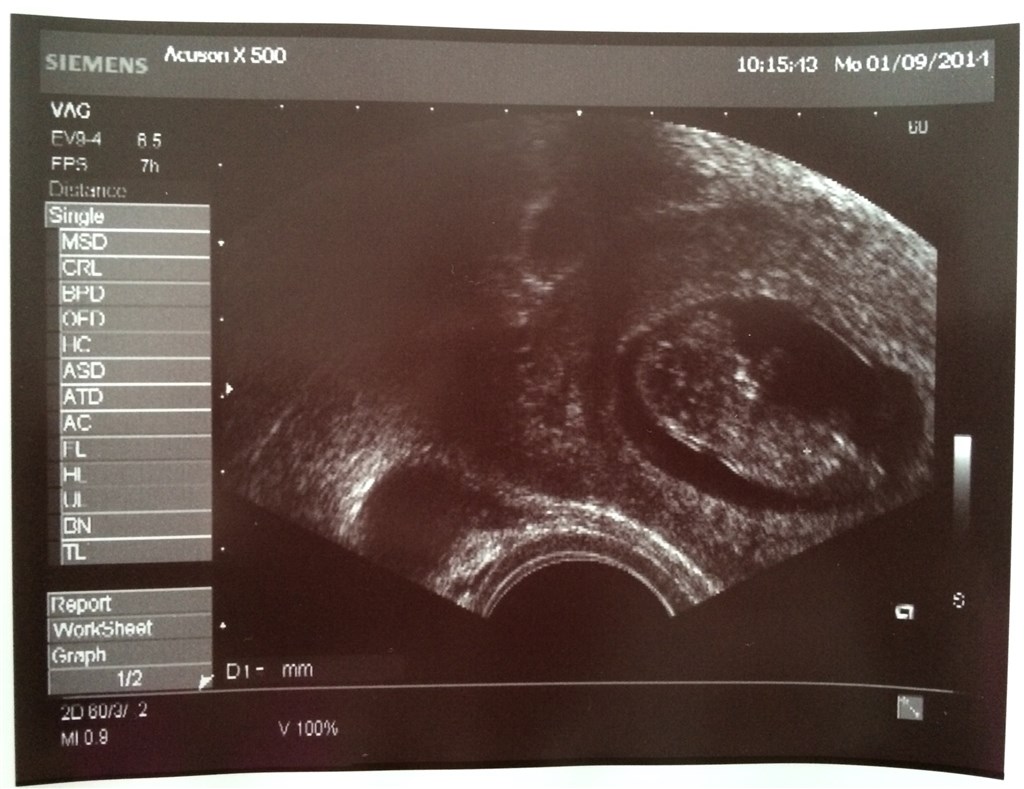

har været til 3 skanninger allerede, de to første var meget tidligt (7+2 & 8+2) , men der var hjerteblink begge gange! Og i dag har vi været til scanning igen er 10+2 og bebs baskede fint med både arme og ben, det var så rørende og livsbekræftende at se!

I får også lige billeder fra scanning i uge 8+2 og 10+2

Vedhæftede fotos (klik for at se i fuld størrelse)